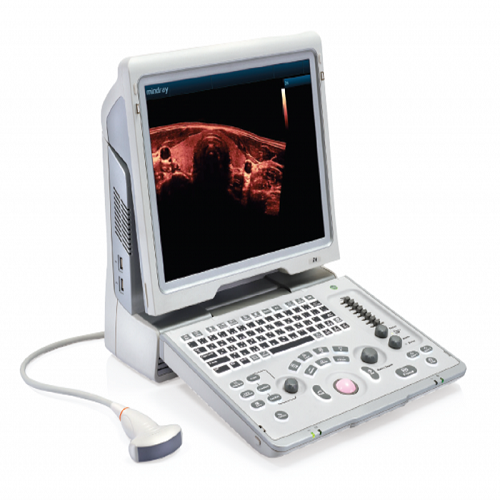

MINDRAY Z6 PORTABLE COLOUR DOPPLER ULTRASOUND

The Z6 portable Colour

Doppler ultrasound system is a well-balanced choice for those who require the

features of traditional Colour Doppler ultrasound system, whilst maintaining

outstanding value for money and portability.

The Z6 system offers amazing image quality and

innovative functionality.

- 15-inch High resolution LCD Monitor

- Screen resolution of 1024x768

- Ability to adjust the angle of the monitor

- Tilting control panel with interactive Back-lighting

- Electronic Trackball

Mindray Z6 Portable Colour Doppler Ultrasound

- Product Code: MR678860